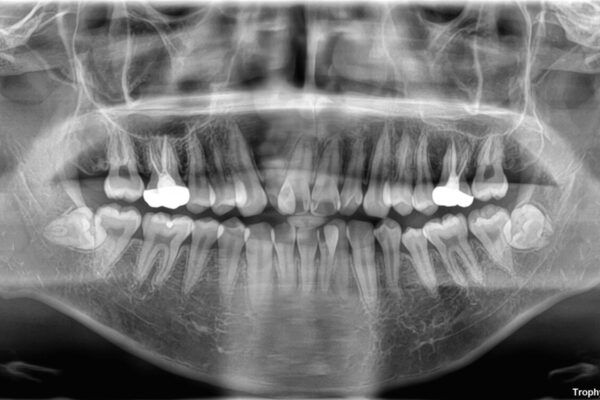

治療途中

• 1年でここまで変わる!歯列のがたつきと正中のズレを改善した矯正治療(メタルブラケット×MARPE) 治療途中画像

・上下ともに歯がきれいに並びきらず、がたつきが見られました。

・上下の前歯の中心(正中)がずれています。

・特に上顎の幅が狭いため、下顎の歯列も内側に入り込み、歯が並ぶスペースが不足していました。

このような歯列の狭さに起因するデコボコを改善するために、**MARPE(骨に固定する上顎急速拡大装置)**を使用して、上顎の横幅を拡大し、これにより歯が並ぶためのスペースを確保し、メタルブラケットを用いて歯列を整えていく計画としました。